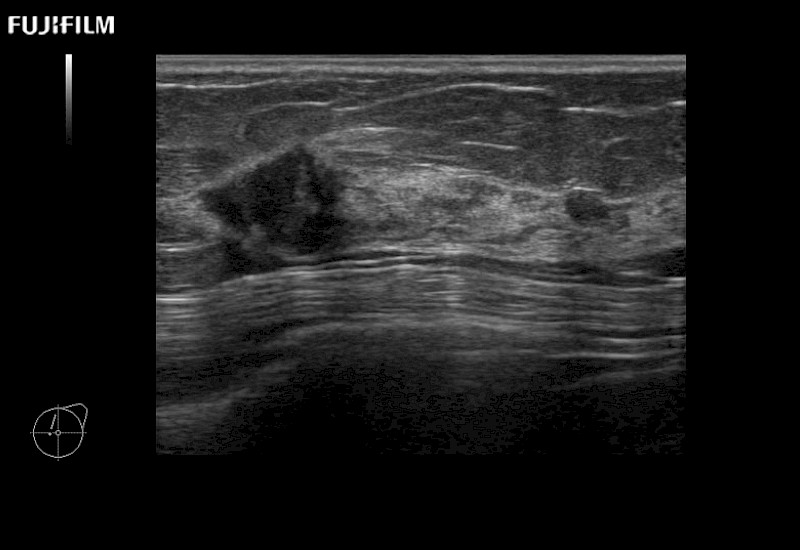

The ARIETTA 750 incorporates all of the proven technologies and functions that medical professionals have come to expect from Fujifilm Healthcare.

ARIETTA 750 is the definitive diagnostic ultrasound solution for any clinical setting - Private Office, Imaging Center, or Hospital. The ARIETTA platform provides the ultimate in clinical performance with its state-of-the-art features and large user-friendly display.

The ARIETTA 650 DI combines trusted Fujifilm Healthcare technologies and features tailored for surgical oncology.

Designed to meet the demands of surgeons, the ARIETTA 650 DI offers precise guidance. Its advanced capabilities and large, intuitive display offer accurate and efficient care in operating rooms and specialized surgical settings.